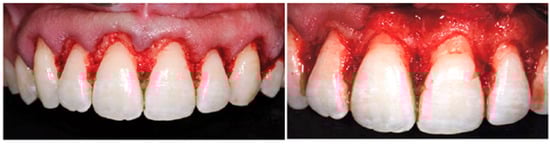

2.4. Surgical Approach and Clinical Recommendations